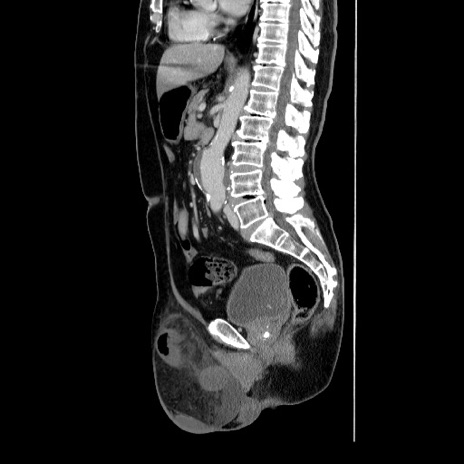

症例34(矢状断像)

【症例】60歳代 男性

【主訴】右鼠径部膨隆

【現病歴】1年程前より右鼠径部膨隆あり。自己にて還納可能だったため放置していた。3時間前より右鼠径部の脱出を認め、還納困難となり受診。

【身体所見】右鼠径部に小児頭大の膨隆あり。弾性硬であり、用手還納は困難。左鼠径部にも膨隆を認める。脱出はなし。